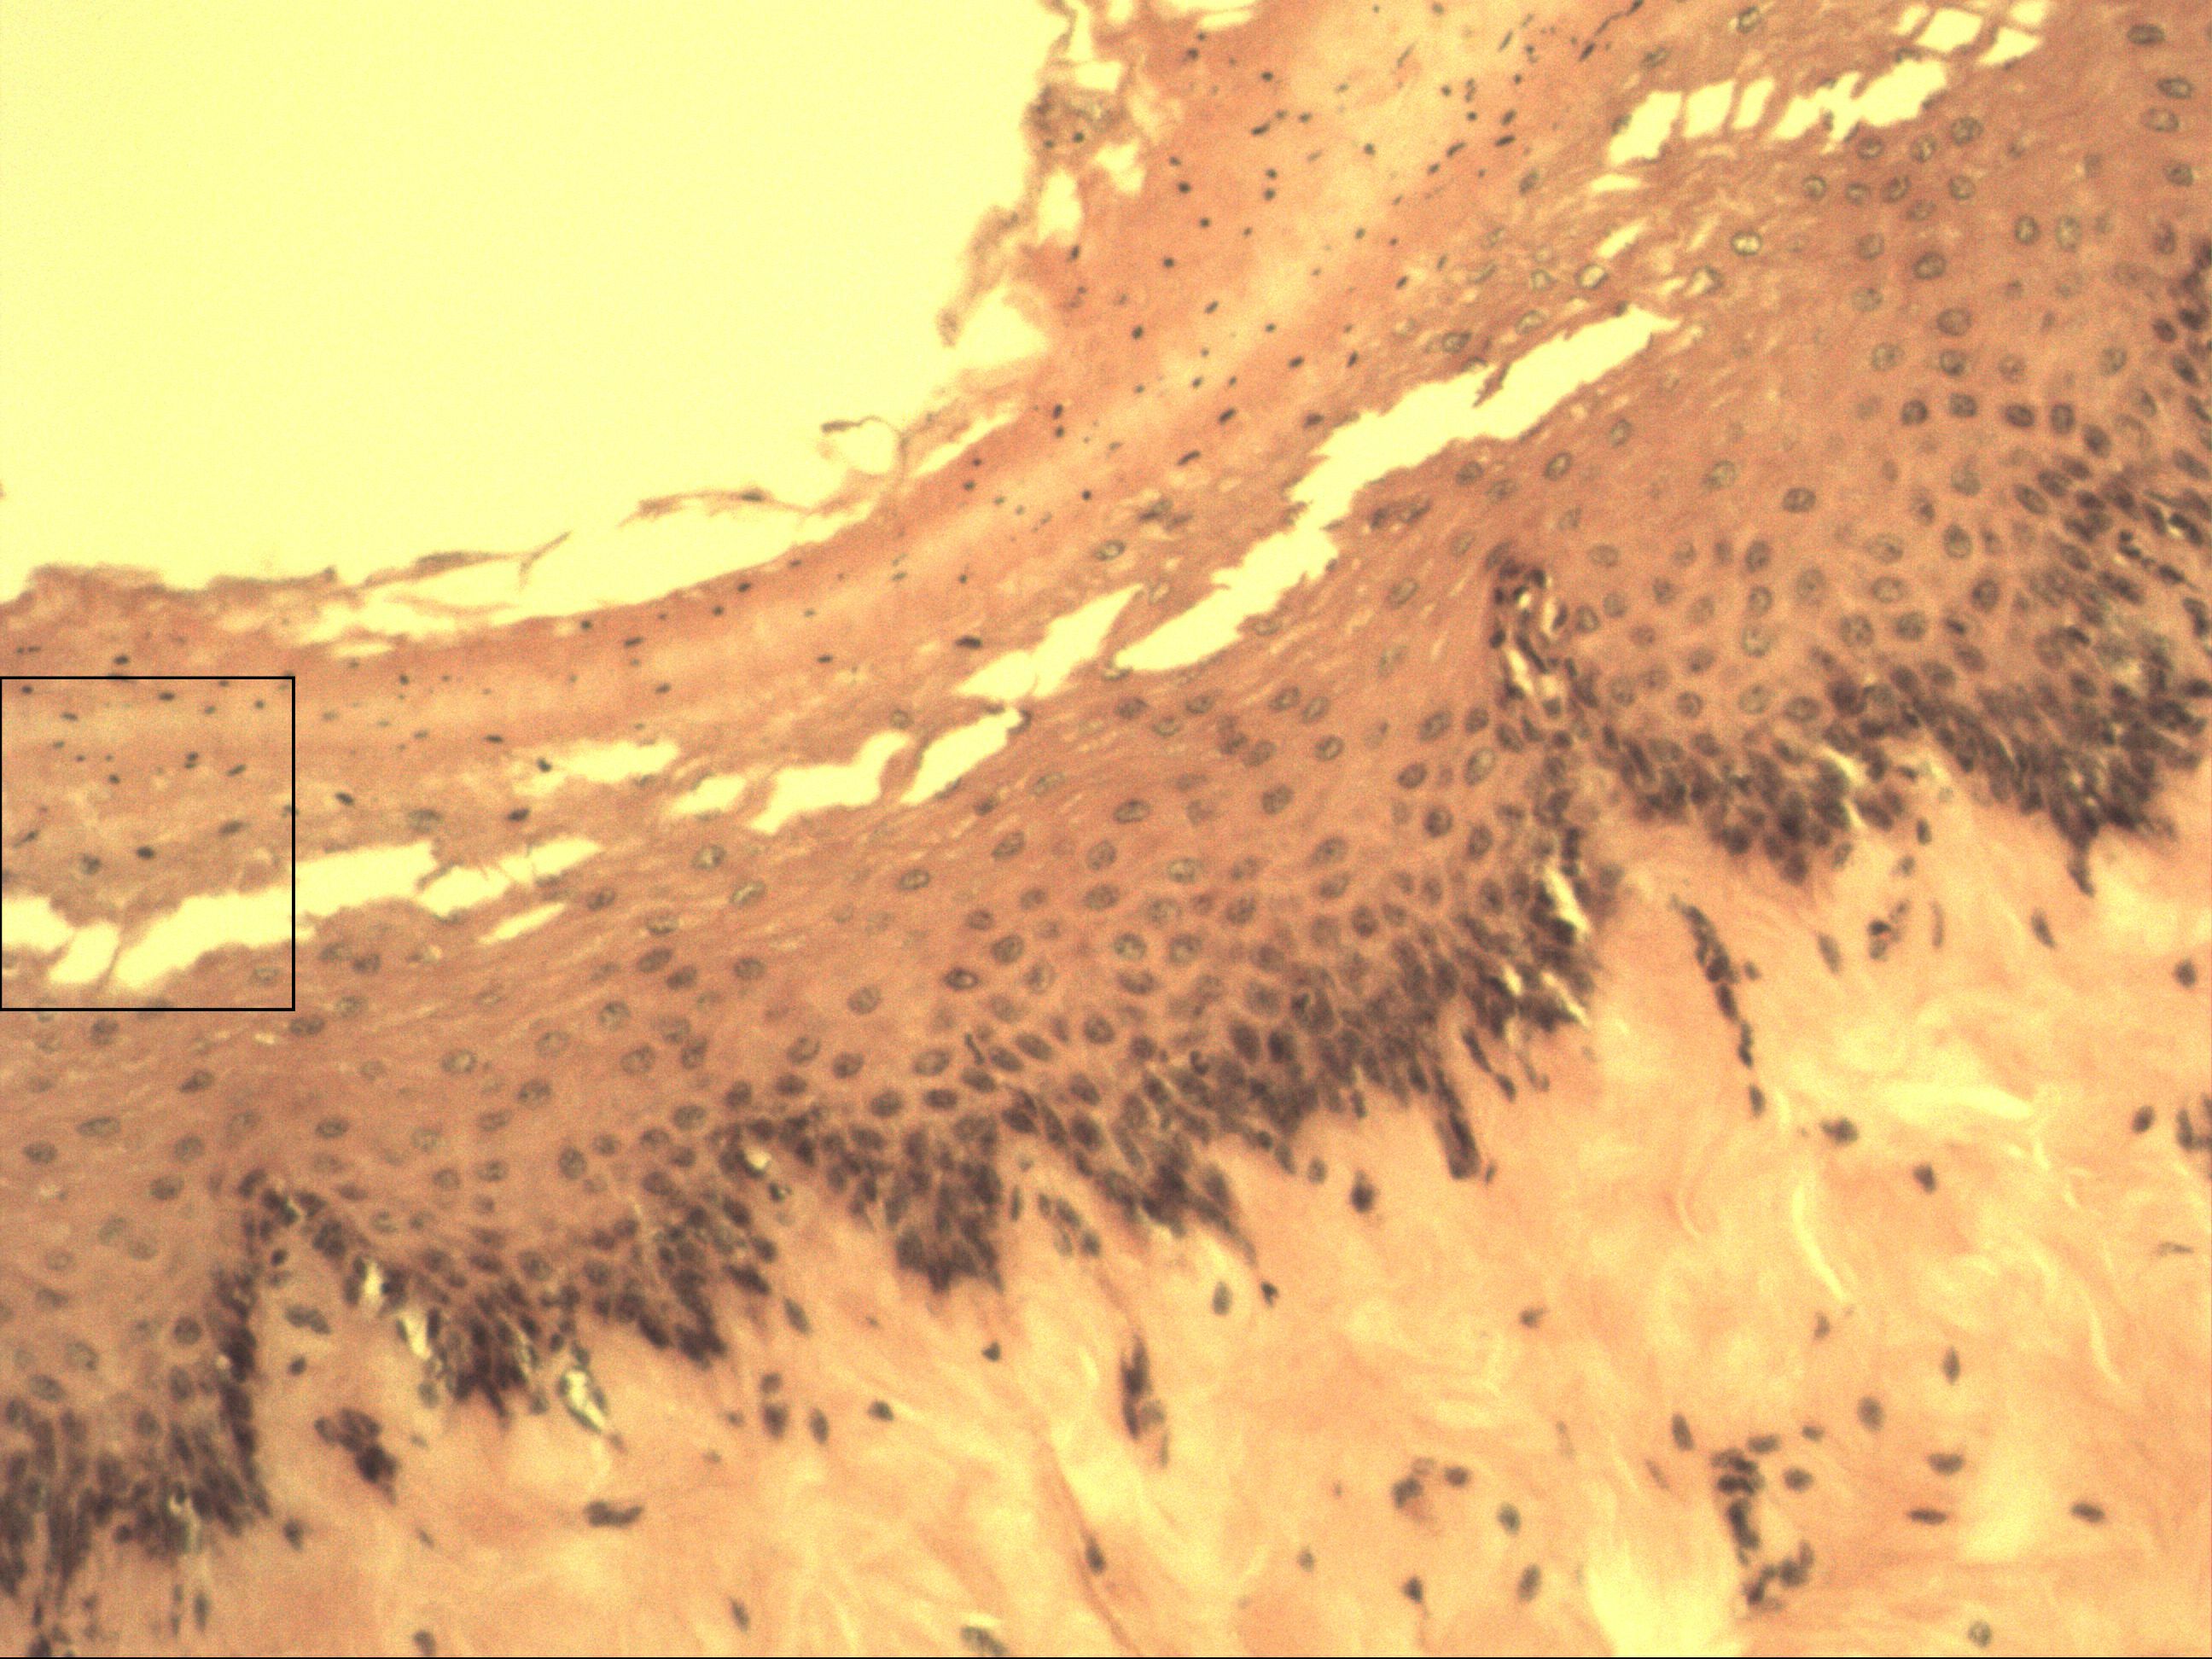

Mehrschichtiges unverhorntes Plattenepithel

Oesophagus [HE]

Das mehrschichtig unverhornte Plattenepithel ist typisch für mechanisch beanspruchte Zonen. Es kommt sowohl in der Speiseröhre und in der Mundhöhle als auch im Analkanal und der Vagina vor. Außerdem in der Horn- und Bindehaut des Auges. Und im letzten Teilabschnitt der männlichen Harnröhre. Man erkennt diese drei Schichten: Stratum basale, Stratum intermedium und Stratum superficiale (mit buckeligen Zellen).